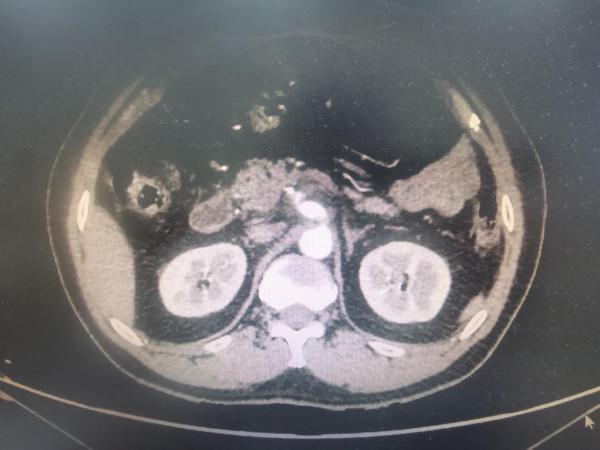

腹部CT是一種圖質好、 診斷價值高而又無創傷、無痛苦的診斷方法。它使我們能夠在任何深度或任何角度重建腹部的各種層面結構。但因為其費用比B超、X片等檢查要高,所以一般作為進一步檢查的專案來選擇。

病例1:患者男性,50歲,突發上腹痛2小時,呈劇烈疼痛,伴有嘔吐,全腹硬如木板。X片:未見腹腔內遊離氣體。腹部CT:肝腎隱窩有少量遊離氣體,空腔臟器穿孔。

這名患者突發劇烈腹痛,全腹硬如木板,最有可能的診斷就是消化道穿孔。但是從機率上統計,大約有20%的患者不能在普通X片上看到遊離氣體,這時候就需要腹部CT進一步檢查,即使能看到腹腔深部的少量的遊離氣體,也可以做出診斷。

病例2:患者男性,58歲,反覆上腹痛半年,在多家醫院就診,反覆查腹部B超、胃鏡、血常規肝功等檢查,不能明確診斷。來我院查腹部增強CT:腹腔幹動脈狹窄。診斷因為血管炎、血管狹窄引起疼痛。

這名患者已經做過多種檢查,但是對於腹腔血管的檢查,普通B超、胃鏡,甚至普通CT平掃都不能有效診斷,但是增強CT可以顯示血管的形態,對於這一類疾病可以給出準確的診斷意見。